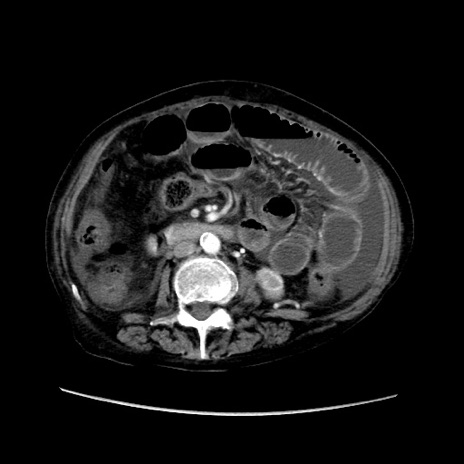

症例31(横断像)

【症例】80歳代 女性

【主訴】腹部膨満感

【現病歴】他院にて肝硬変にてフォロー中。1週間前から便秘、腹部膨満感、臍部腫瘤あり受診となる。

【既往歴】肝硬変

【身体所見】腹部膨隆あり、皮膚変化なし、疼痛なし。

【データ】WBC 4600、CRP 0.25